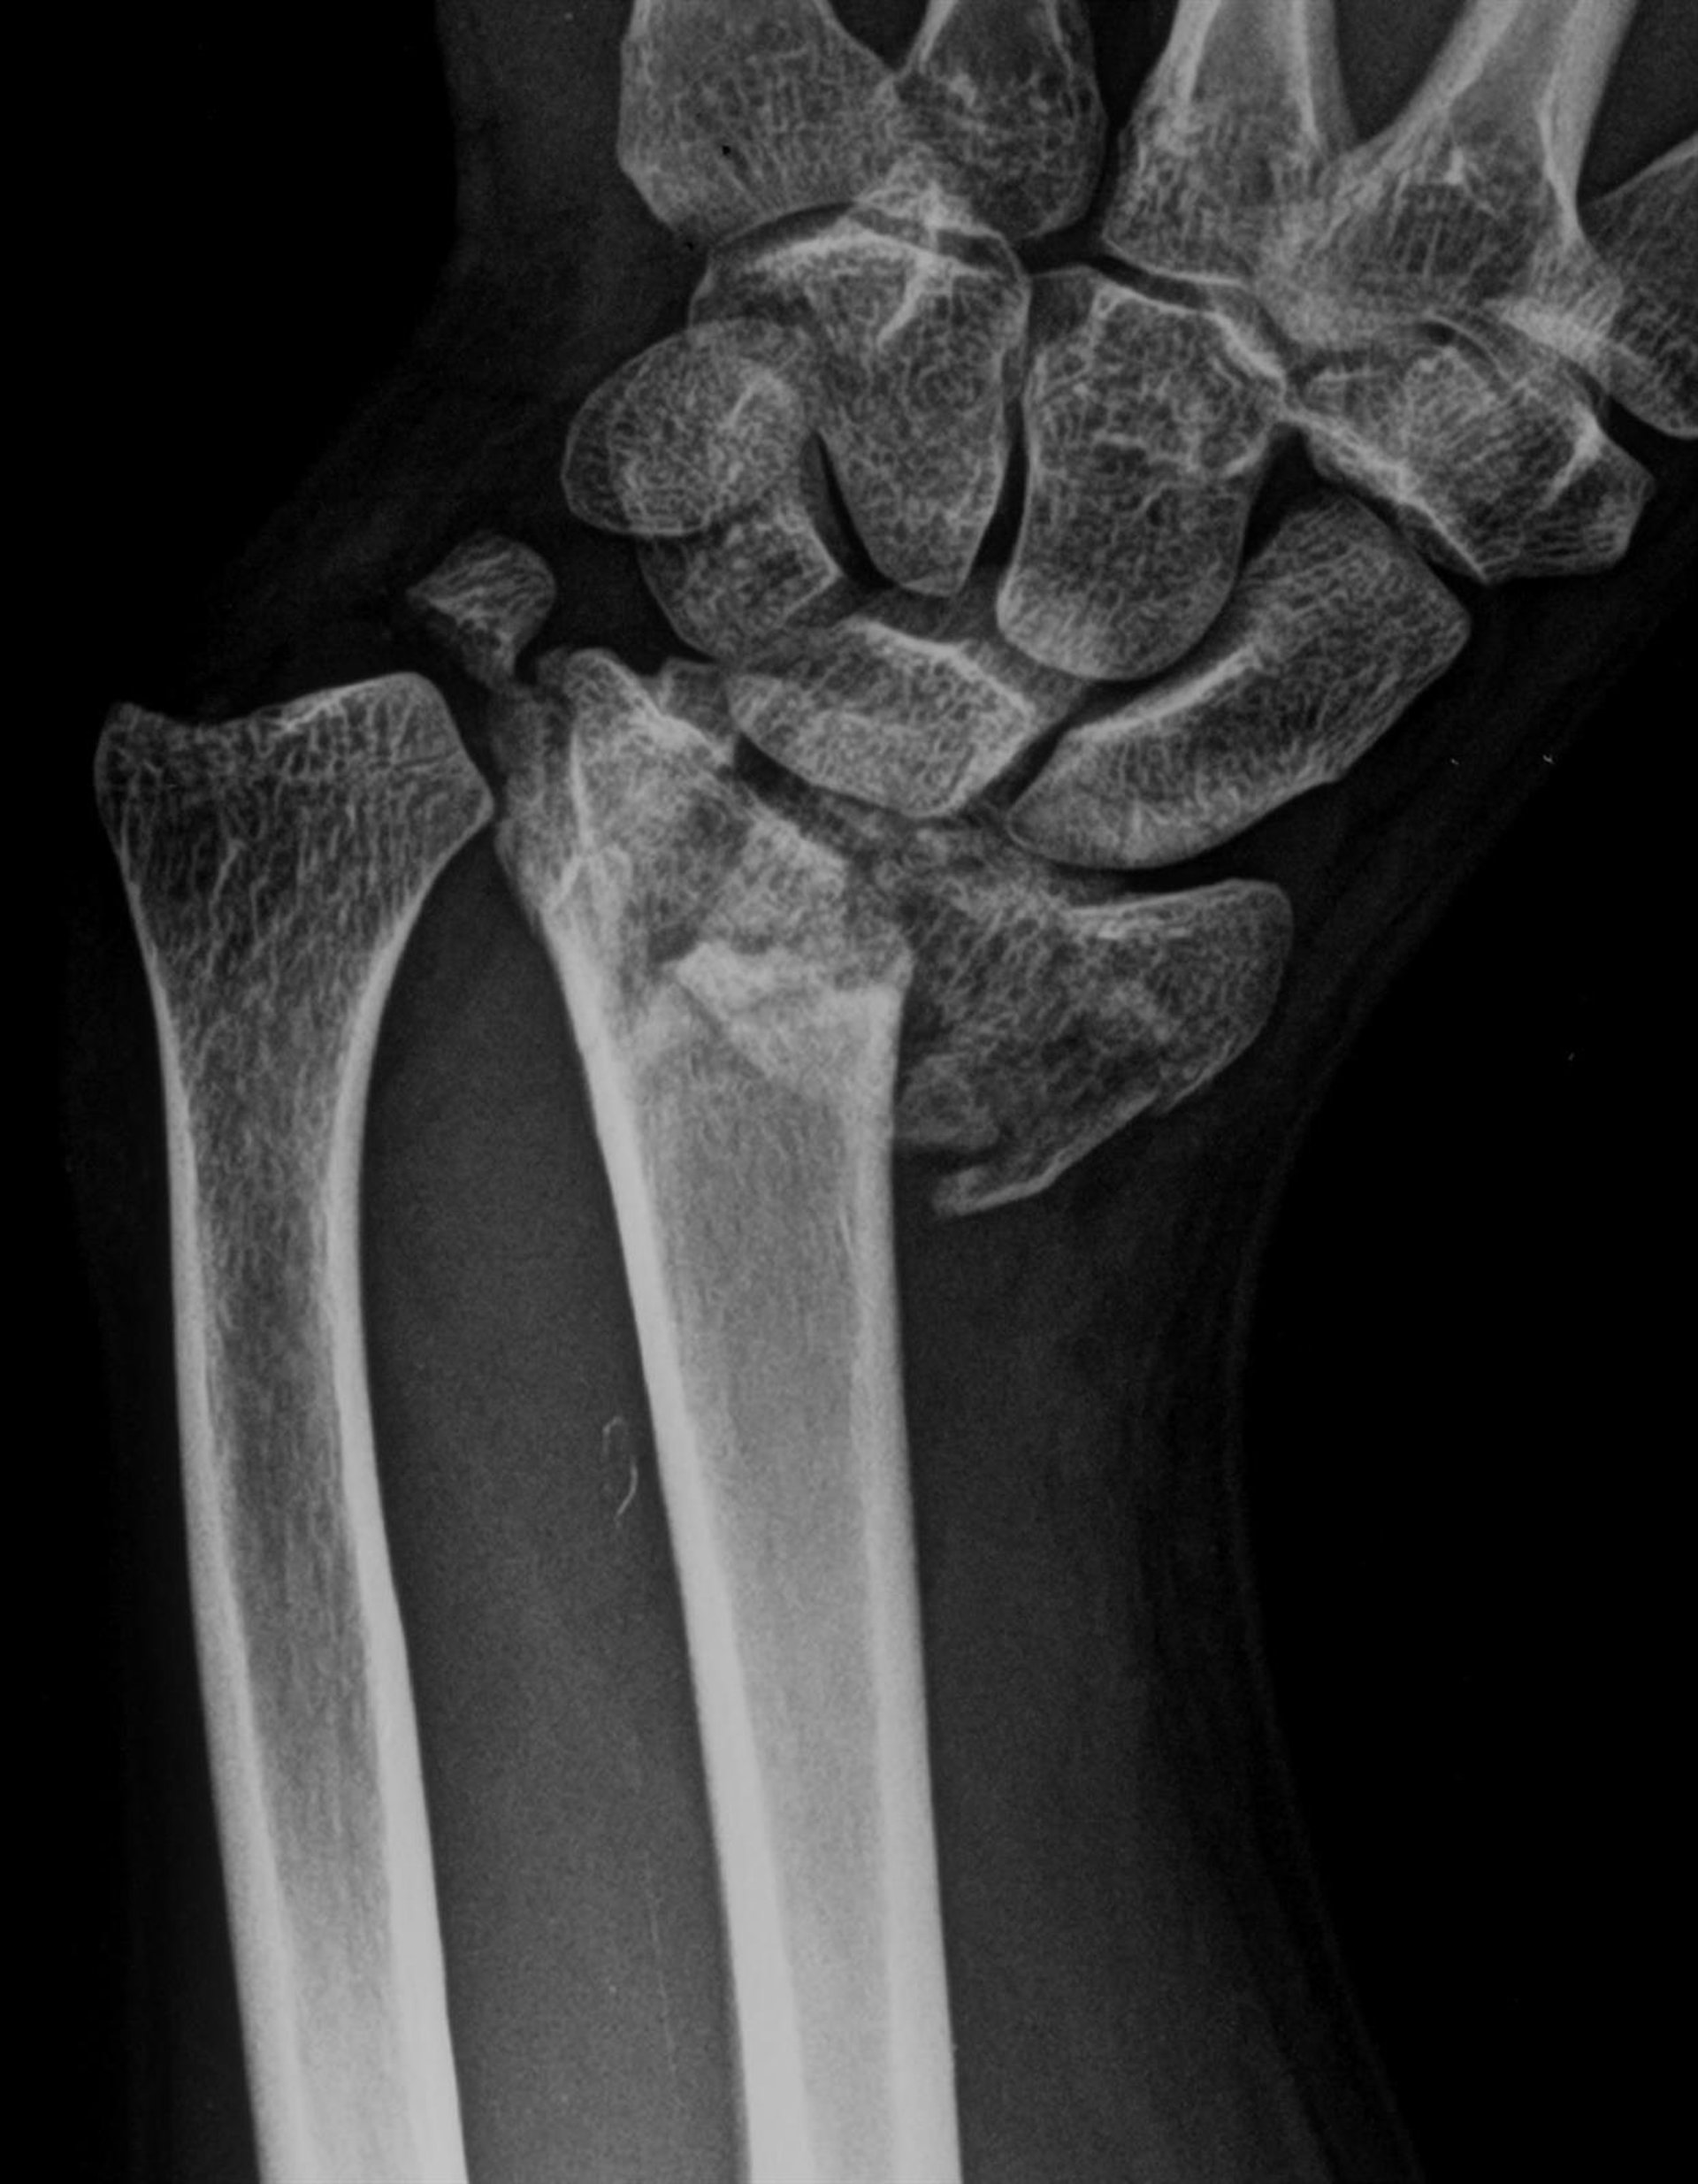

Fractura de radio

Fractura de radio - HOSPITAL LA LUZ - Archivo

Se calcula que uno de cada cinco hombres y una de cada tres mujeres mayores de 50 años son propensos a tener una fractura osteoporótica. Las más comunes ocurren en la columna vertebral, la muñeca y la cadera. Pueden ser mortales o causar discapacidad a largo plazo. Sin embargo, en la actualidad esta enfermedad puede prevenirse, diagnosticarse y controlarse.